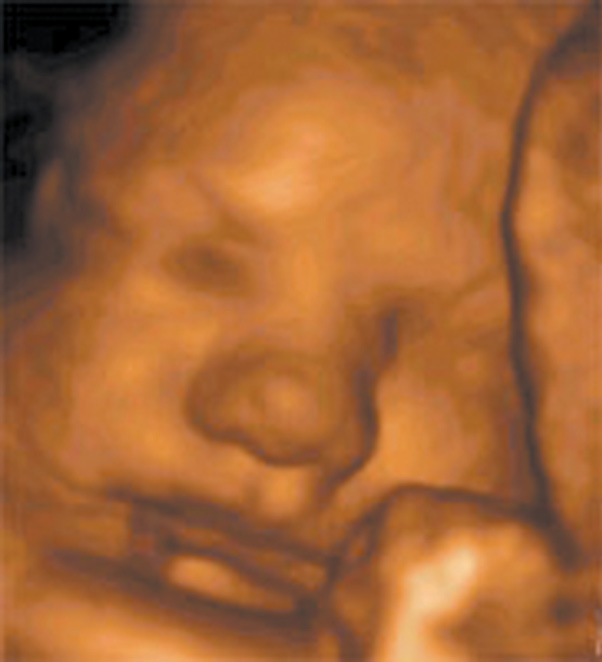

Цель 3D-ультразвукового исследования состоит в создании объемного изображения в отличие от двухмерного метода, создающего плоскостные сечения [6, 11]. Объемная картина получается при сканировании смежных сечений — это объем пространства пирамидальной формы (рис. 3, 4).

Рис. 3. Плод, 31 неделя, 3D-ультразвуковое исследование / Fig. 3. Fetus, 31 weeks, 3D

На полученных сонограммах у 15 беременных визуализировались все 20 зубных зачатков. Лицо плода помещалось на экран таким образом, чтобы можно было вывести профиль, а сдвиг и вращение изображения давали возможность осмотра верхней и нижней челюсти (рис. 8, 9). У трех беременных визуализация была затруднена. С использованием плоскостей сканирования, оптимизированных для исследования конкретного органа, осуществлялась визуализация нижней челюсти целиком, включая сочленение с верхней челюстью.

Рис. 8. Лицо плода / Fig. 8. Fetal face